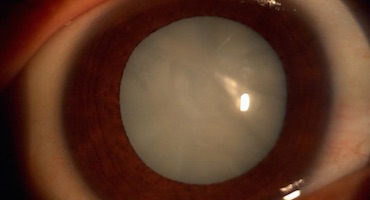

Una catarata es la opacidad que se produce en el cristalino del ojo y que provoca que la visión del paciente sea nublada, como la que uno tendría si mirara por una ventana empañada. Son la primera causa de ceguera prevenible a nivel mundial y, en Costa Rica, un problema de salud pública por la gran cantidad de pacientes que presentan esta condición.

Las cataratas se forman debido a que, con el envejecimiento, o por una lesión, el tejido que forma el lente del ojo cambia. El lente se encuentra detrás de la parte coloreada del ojo y es el encargado de focalizar la luz que ingresa para producir imágenes nítidas en la retina. Las cataratas, conforme van creciendo, bloquean la luz que pasa a través del lente, por lo que las imágenes que recibe la retina se van tornando más borrosas.